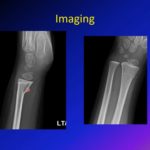

Torus Fractures (Buckle fractures)

Courtesy: Amr Abdelgawad, Maimonaides Medical Centre, Brooklyn, NY, USA

Distal Tibia and Transitional Fractures in Children